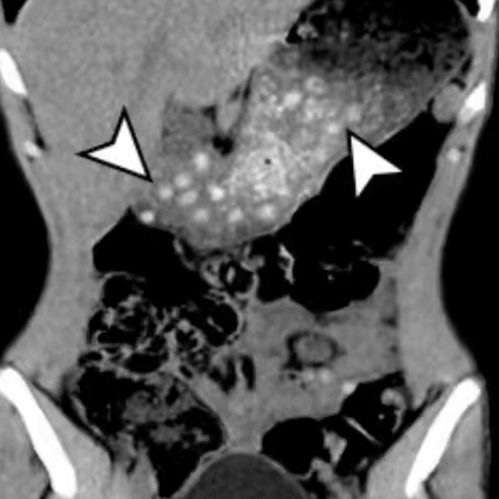

手术中,李主任发现穿孔位于乙状结肠下段,距离直肠肛门很近,在穿孔部位以上部分节段肠管已经出现缺血坏死,穿孔处周围有积液,并有腹膜炎症表现。手术进行约2小时,切除了穿孔及缺血段肠管,并放置了两根腹腔引流管引流炎症性腹腔积液,术后安返ICU,转危为安。

在医院急诊经常有枣核穿破胃十二指肠、鱼刺卡喉、鱼刺刺穿食管、杨梅核引发肠梗阻的病人前来就医,但误吞的枣核顺利通过管腔较细的食管和小肠,刺破乙状结肠的病例还是少数。